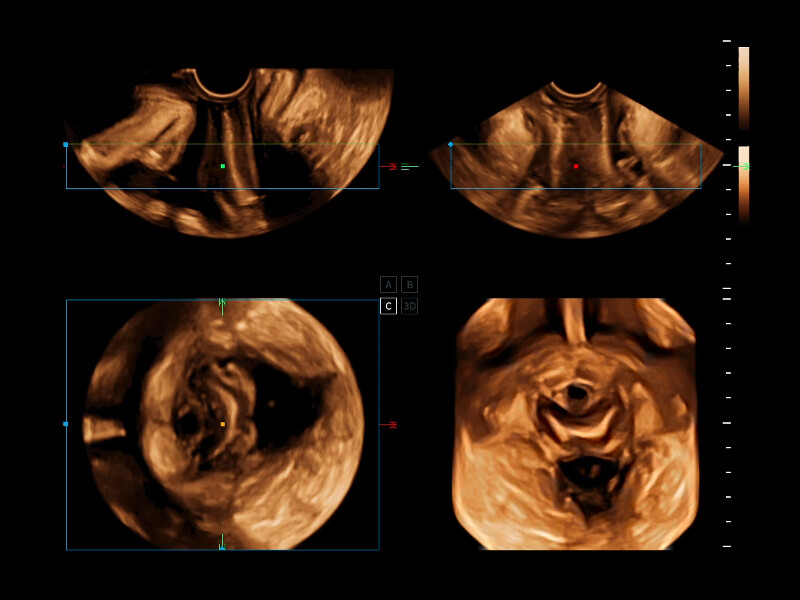

夢(mèng)溪?P80以“關(guān)愛(ài)女性”為基石,提供全方位的解決方案,量身定制以滿(mǎn)足女性的健康需求,涵蓋婦科、生殖健康檢查、產(chǎn)前篩查及產(chǎn)后康復(fù)等領(lǐng)域。

通過(guò)工作流協(xié)議、遠(yuǎn)程訪(fǎng)問(wèn)、自動(dòng)探頭激活和人體工程學(xué)優(yōu)化設(shè)計(jì)等功能,旨在提高臨床工作效率